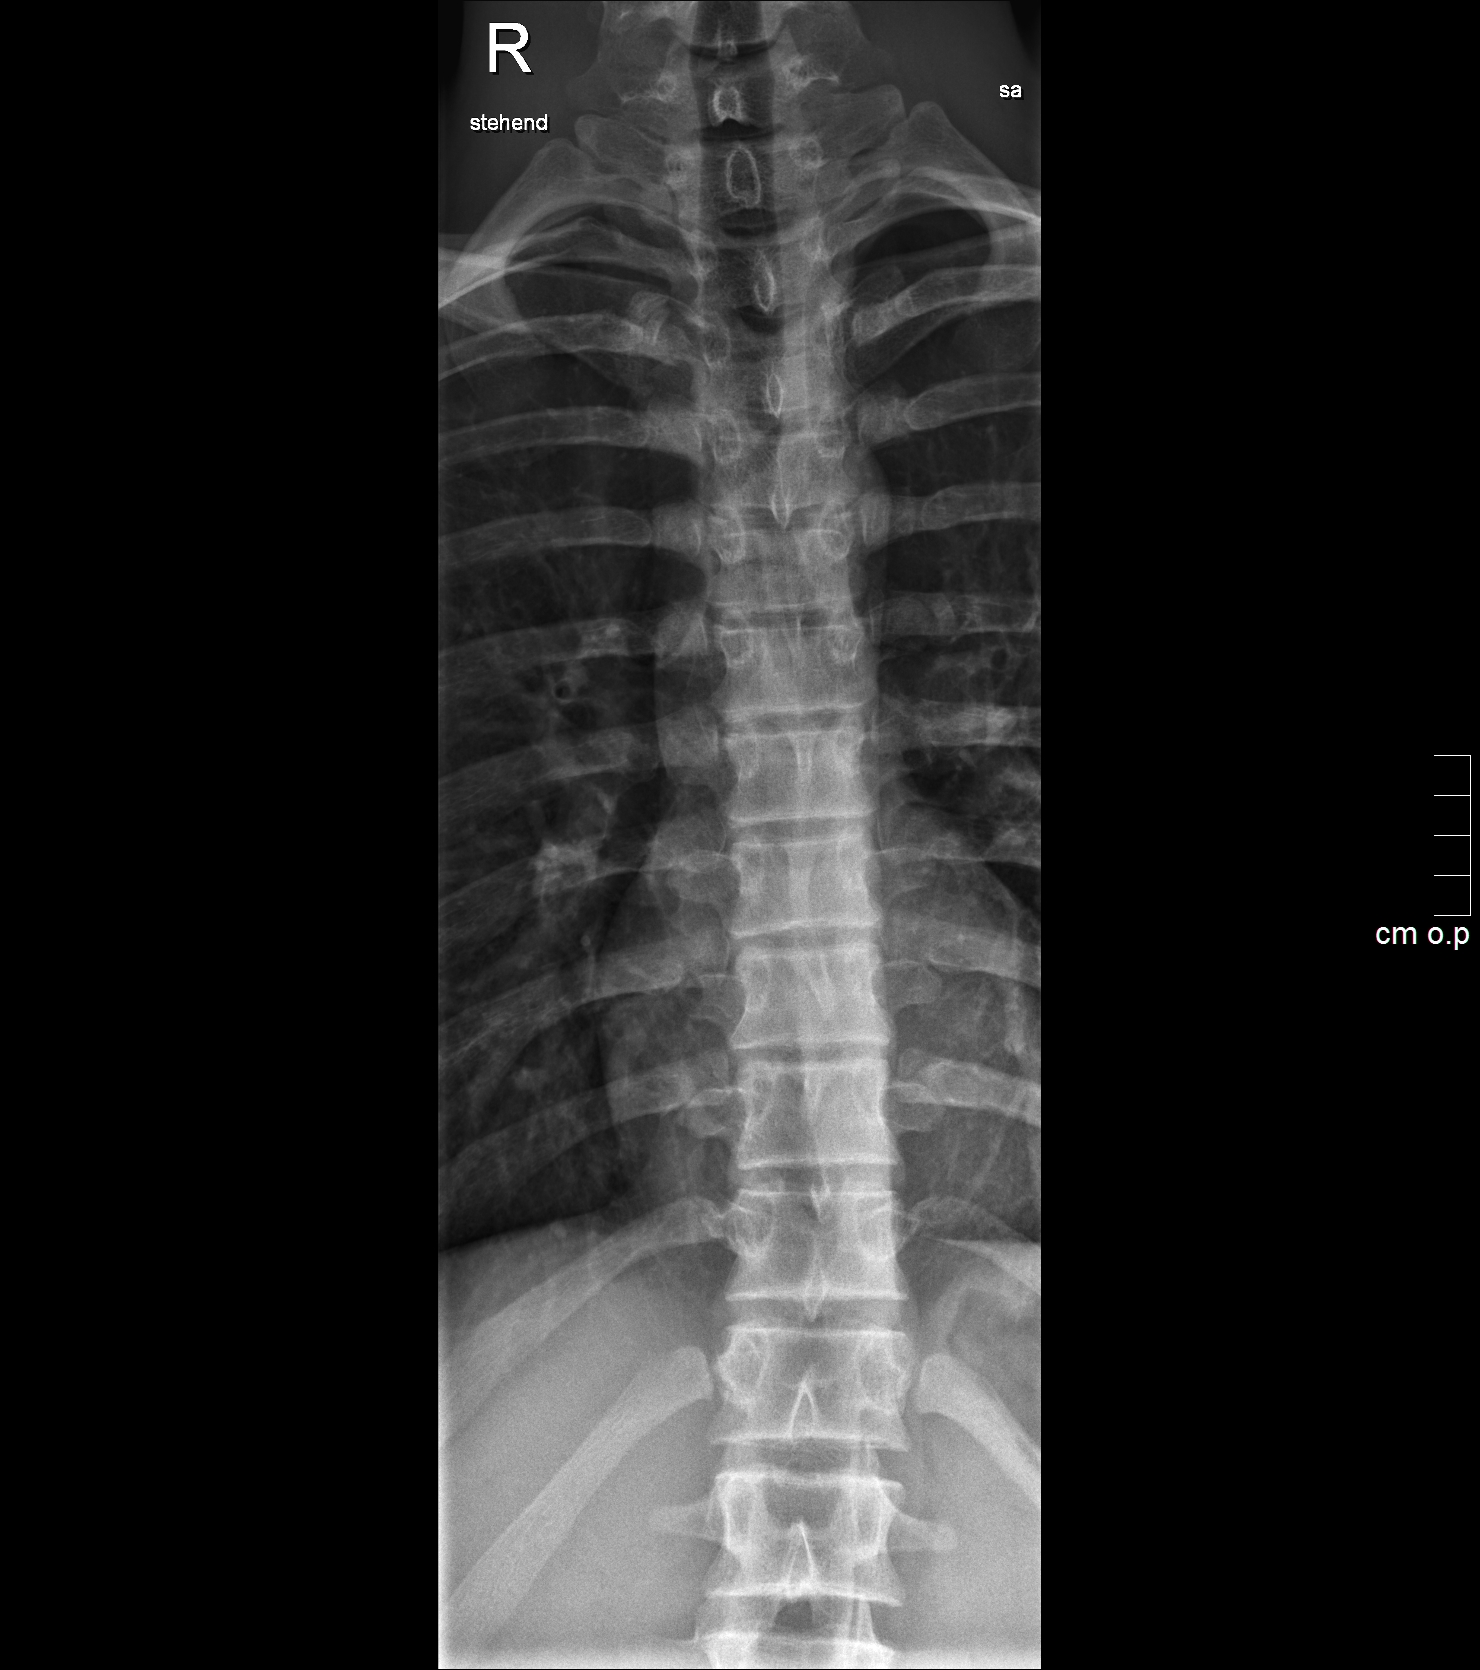

• Wirbelsäulengesamtaufnahme